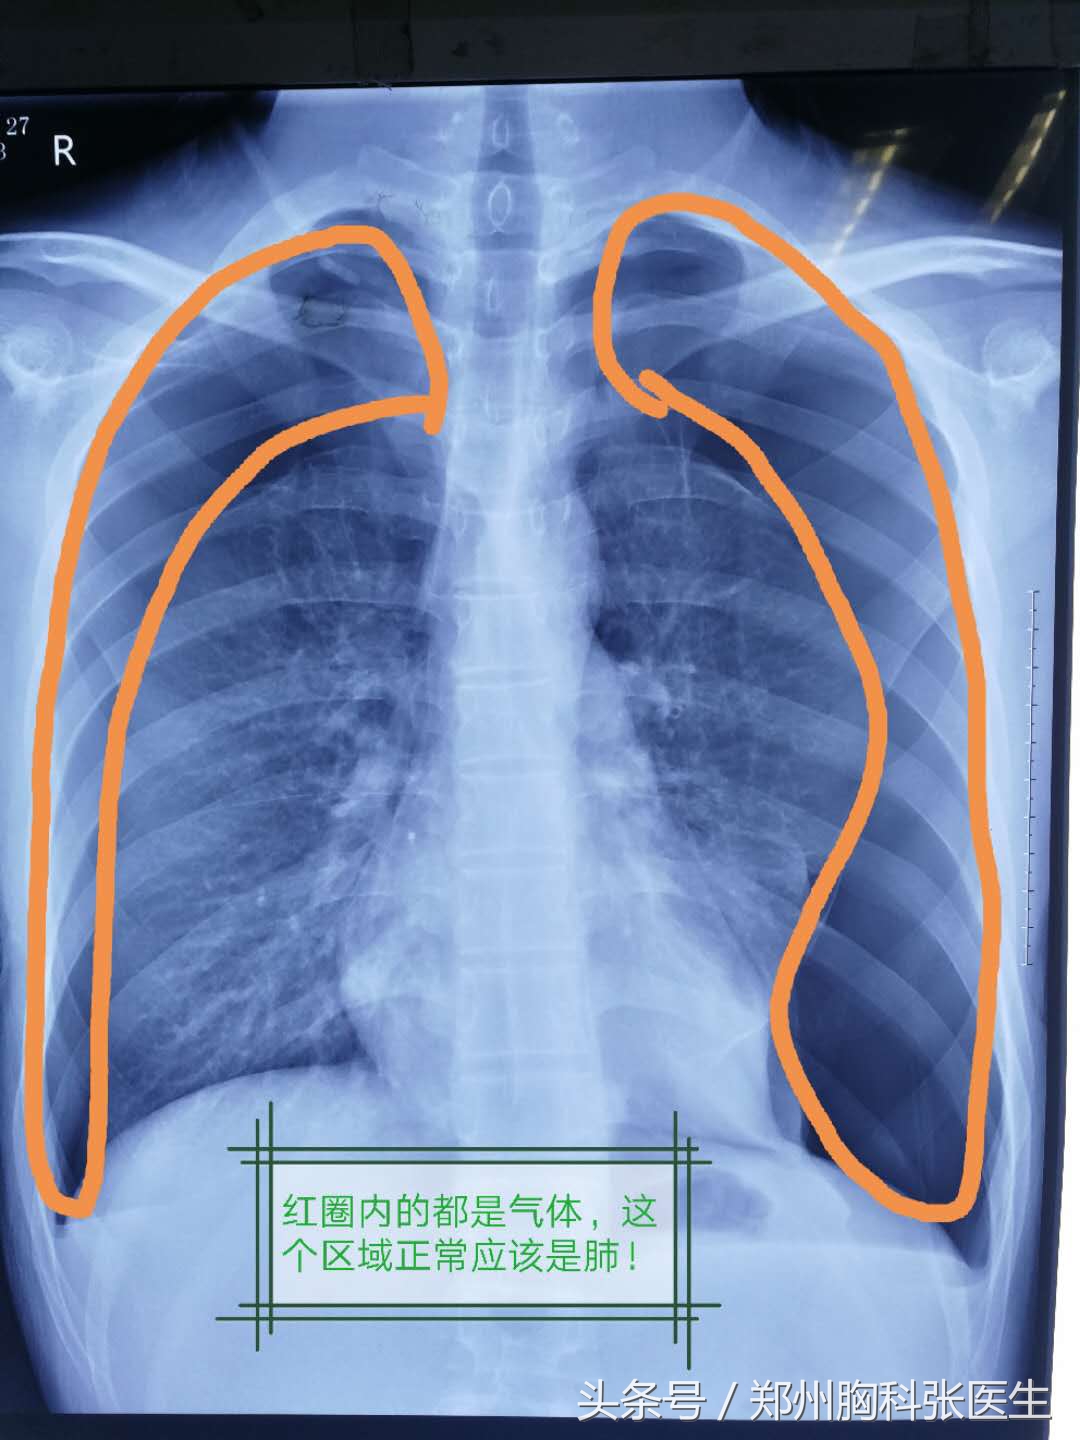

这是一个双侧气胸的患者,也是大老远的由家乡跑来省城医院看病!

这位就是开头说到的那位双侧气胸的小帅哥,一般都是一侧气胸,一个小管即可!